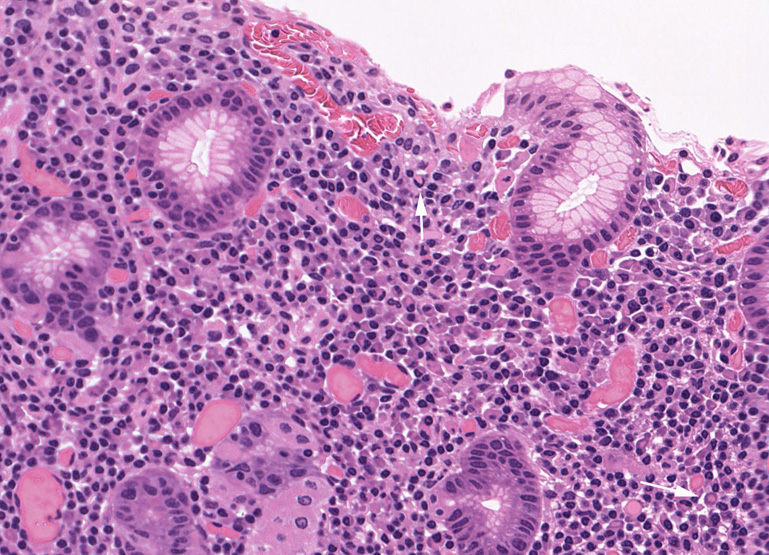

Lymphoepithelial lesion(LEL)

胃MALT lymphomaに認められたlymphoepithelial lesion

腫瘍リンパ球の浸潤で腺窩がボロボロに破壊されている